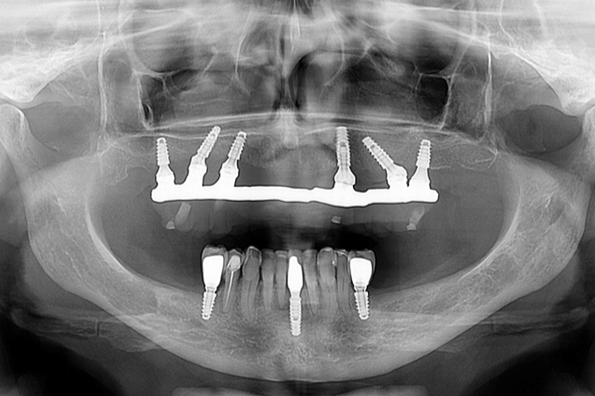

A perda óssea, denominada saucerização, é um processo que ocorre em implantes osseointegrados, principalmente os de plataforma hexagonal externa e que não dependem necessariamente da condição geral do paciente. Perdas ósseas mínimas (entre 1 mm e 2 mm) são consideradas relativamente normais em implantes de plataforma hexagonal externa. Contudo, estudos realizados através de avaliações radiográficas constataram que o emprego da plataforma switching mantém os níveis da crista óssea estáveis com uma perda de osso mínima nesta área do hexágono2.

Muitos autores consideram os implantes conhecidos como Cone Morse como sendo implantes de plataforma switching, pois o verdadeiro conceito Cone Morse, descrito na Engenharia, é muito difícil de ser obtido na Implantodontia. Na verdade, os implantes Cone Morse também procuram aumentar a área de transição entre o implante e o pilar através de uma diminuição da largura dos componentes protéticos. As vantagens são exatamente as mesmas: proporcionar uma melhor área para a acomodação dos componentes do espaço biológico e evitar perdas ósseas precoces. As Figuras 1 a 4 ilustram o conceito de plataforma switching.